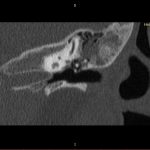

- Diagnosticul traumatismelor de bază de craniu

- Diagnosticul fracturilor:

- Cu înfundare

- Complexe cranio-sinusale

- Complexe cranio-etmoidale

- Complexe cranio-orbitare

- Complexe cranio-faciale